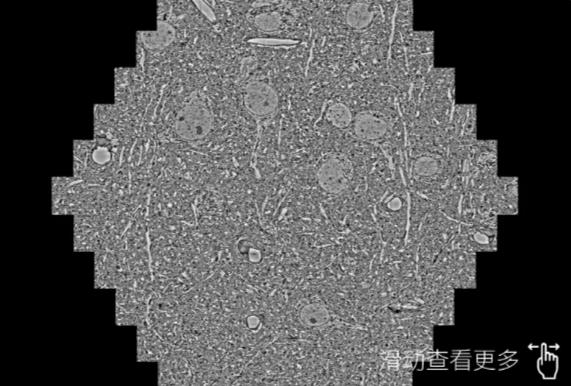

鼠脑切片。左图使用东方蔡司东方扫描电镜MultiSEM706对165μmx143pm面积区域成像,耗时仅需1.5秒。右图为鼠脑切片中30μm区域放大效果。样品由芝加哥大学B.Kasthuri提供。

使用蔡司高速东方扫描电镜MultiSEM对1mm²人脑皮层组织进行高分辨成像,并对其中的各种细胞结构进行三维重构分析。左图展示了2x3mm²组织平面中锥体神经元的三维重构效果。右图显示了局部体积神经元三维重构。图像由哈佛大学chtman实验室提供,渲染图由D. Berger 制作。